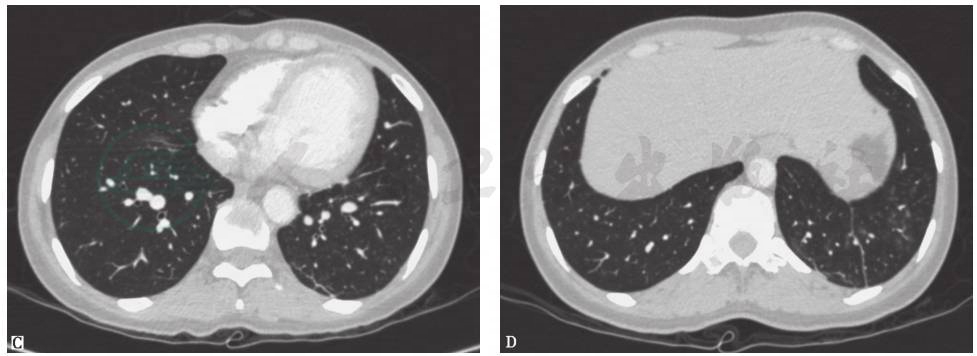

血管炎、系统性红斑狼疮、白塞病等疾病进展累及肺部时,患者可出现发热、咯血等症状,肺内可出现多灶、多形态病灶。其中,白塞病是一种可累及全身的血管炎性疾病,最常见的表现为反复口腔溃疡、生殖器溃疡和虹膜炎,肺部表现包括肺动脉瘤、肺动脉栓塞、肺部结节(图6)、磨玻璃影、胸膜肥厚、胸腔积液、淋巴结增大、肺气肿或肺大疱。本例患者有白塞病家族史,故应警惕该病。

图6 白塞病胸部影像学表现

男性患者,32岁,主因发热、咳嗽、咯血、体重下降2个月入院;反复出现口腔溃疡、生殖器溃疡、下肢结节性红斑,皮肤针刺试验阳性;肺部实变活检提示出血、机化性血栓、血管增生。胸部X线片可见双肺多发斑片影伴左侧胸腔积液(A);胸部CT提示双肺多发结节、实变,左侧胸腔积液(B)。诊断为白塞病